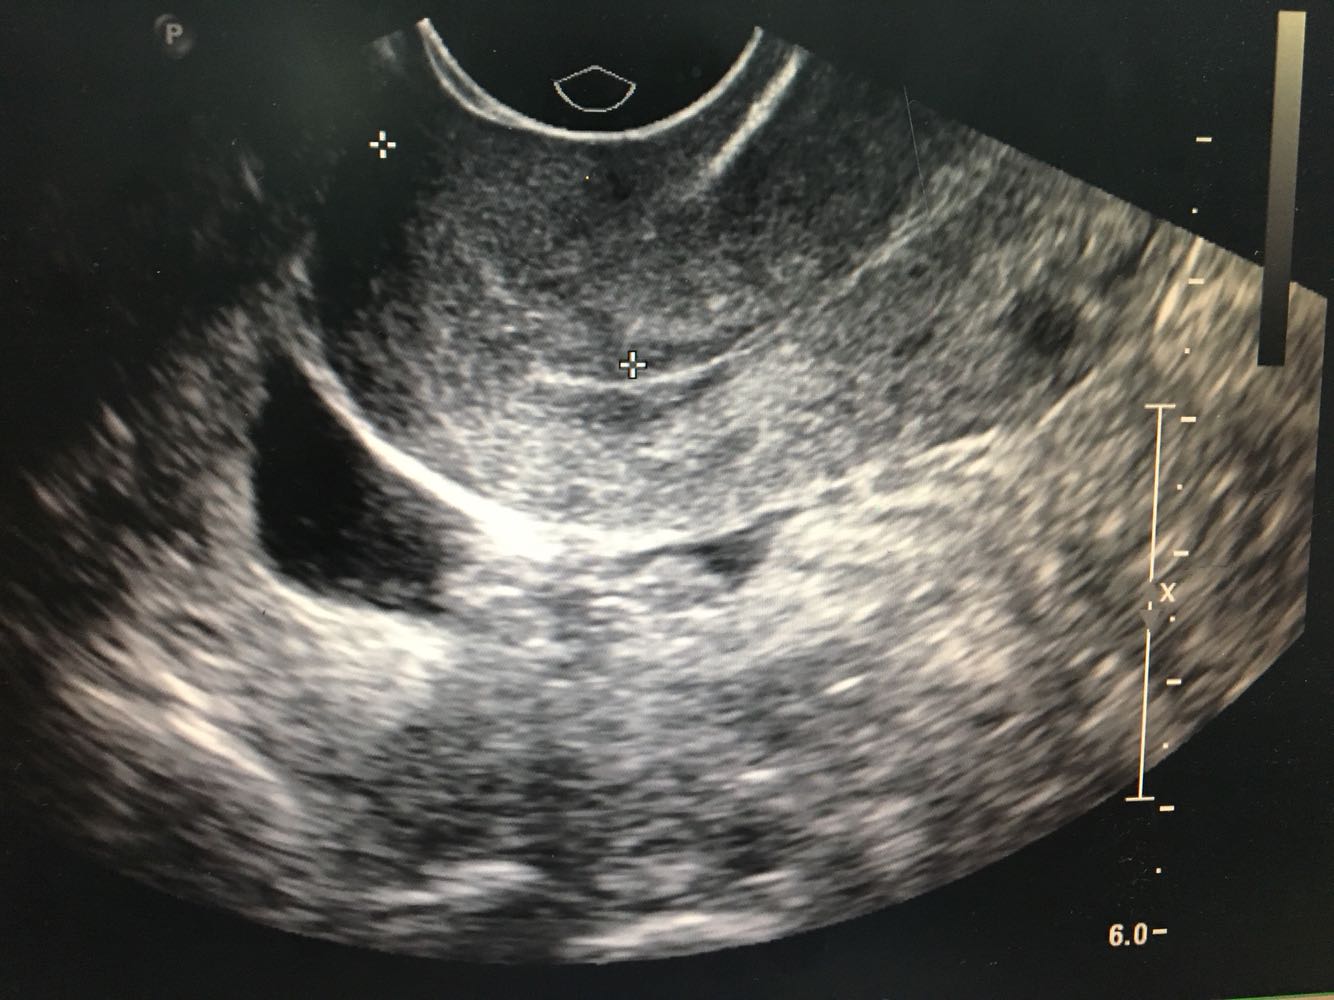

1.患者,女,35岁     2.主诉:人流后经量减少伴痛经7月余 3.现病史:0-0- 2-0,初潮14岁,既往5/25,经量中等,无痛经。患者于2016年12月行人工流产术,术后1月月经正常来潮,2017年1月起出现明显经量减少,经期缩短伴下腹坠痛,自行服用中药调理(具体药物不明),未见明显好转。2017年4月就诊外院,B超诊断为宫颈粘连(报告未见),当时未予特殊处理。患者经量仍有减少,经期缩短至1天,腹痛症状逐渐加重,无腹泻,无恶心呕吐,无畏寒发热等不适。遂就诊我院B超示子宫内膜回声不均匀,宫腔部分粘连可能;小型子宫肌瘤;盆腔积液;右附件系膜囊肿。现患者有生育要求,为寻求进一步治疗,拟“人工流产后宫腔粘连”收治入院。病程中患者无异常阴道流血流液,无经期间出血,无发热,无恶心呕吐。

诊断: 流产后宫腔粘连(可能);子宫平滑肌瘤(小型) 诊疗方案:患者入院后完善各项检查,麻醉下行宫腔镜下宫腔粘连分解+刮宫术,术中见:宫颈管形态正常,宫腔上1/3宫底处粘连,左右两侧壁膜状轻度粘连,双侧输卵管未见。以剪刀剪开宫底处粘连使宫底处展平,暴露双侧输卵管开口清晰,剪除左右两侧壁膜状粘连带,使宫腔恢复正常形态。刮匙沿宫腔四壁轻柔搔刮,刮出少量内膜送病理。手术顺利,术后给予抗炎治疗,观察阴道出血少,患者生命体征平稳。